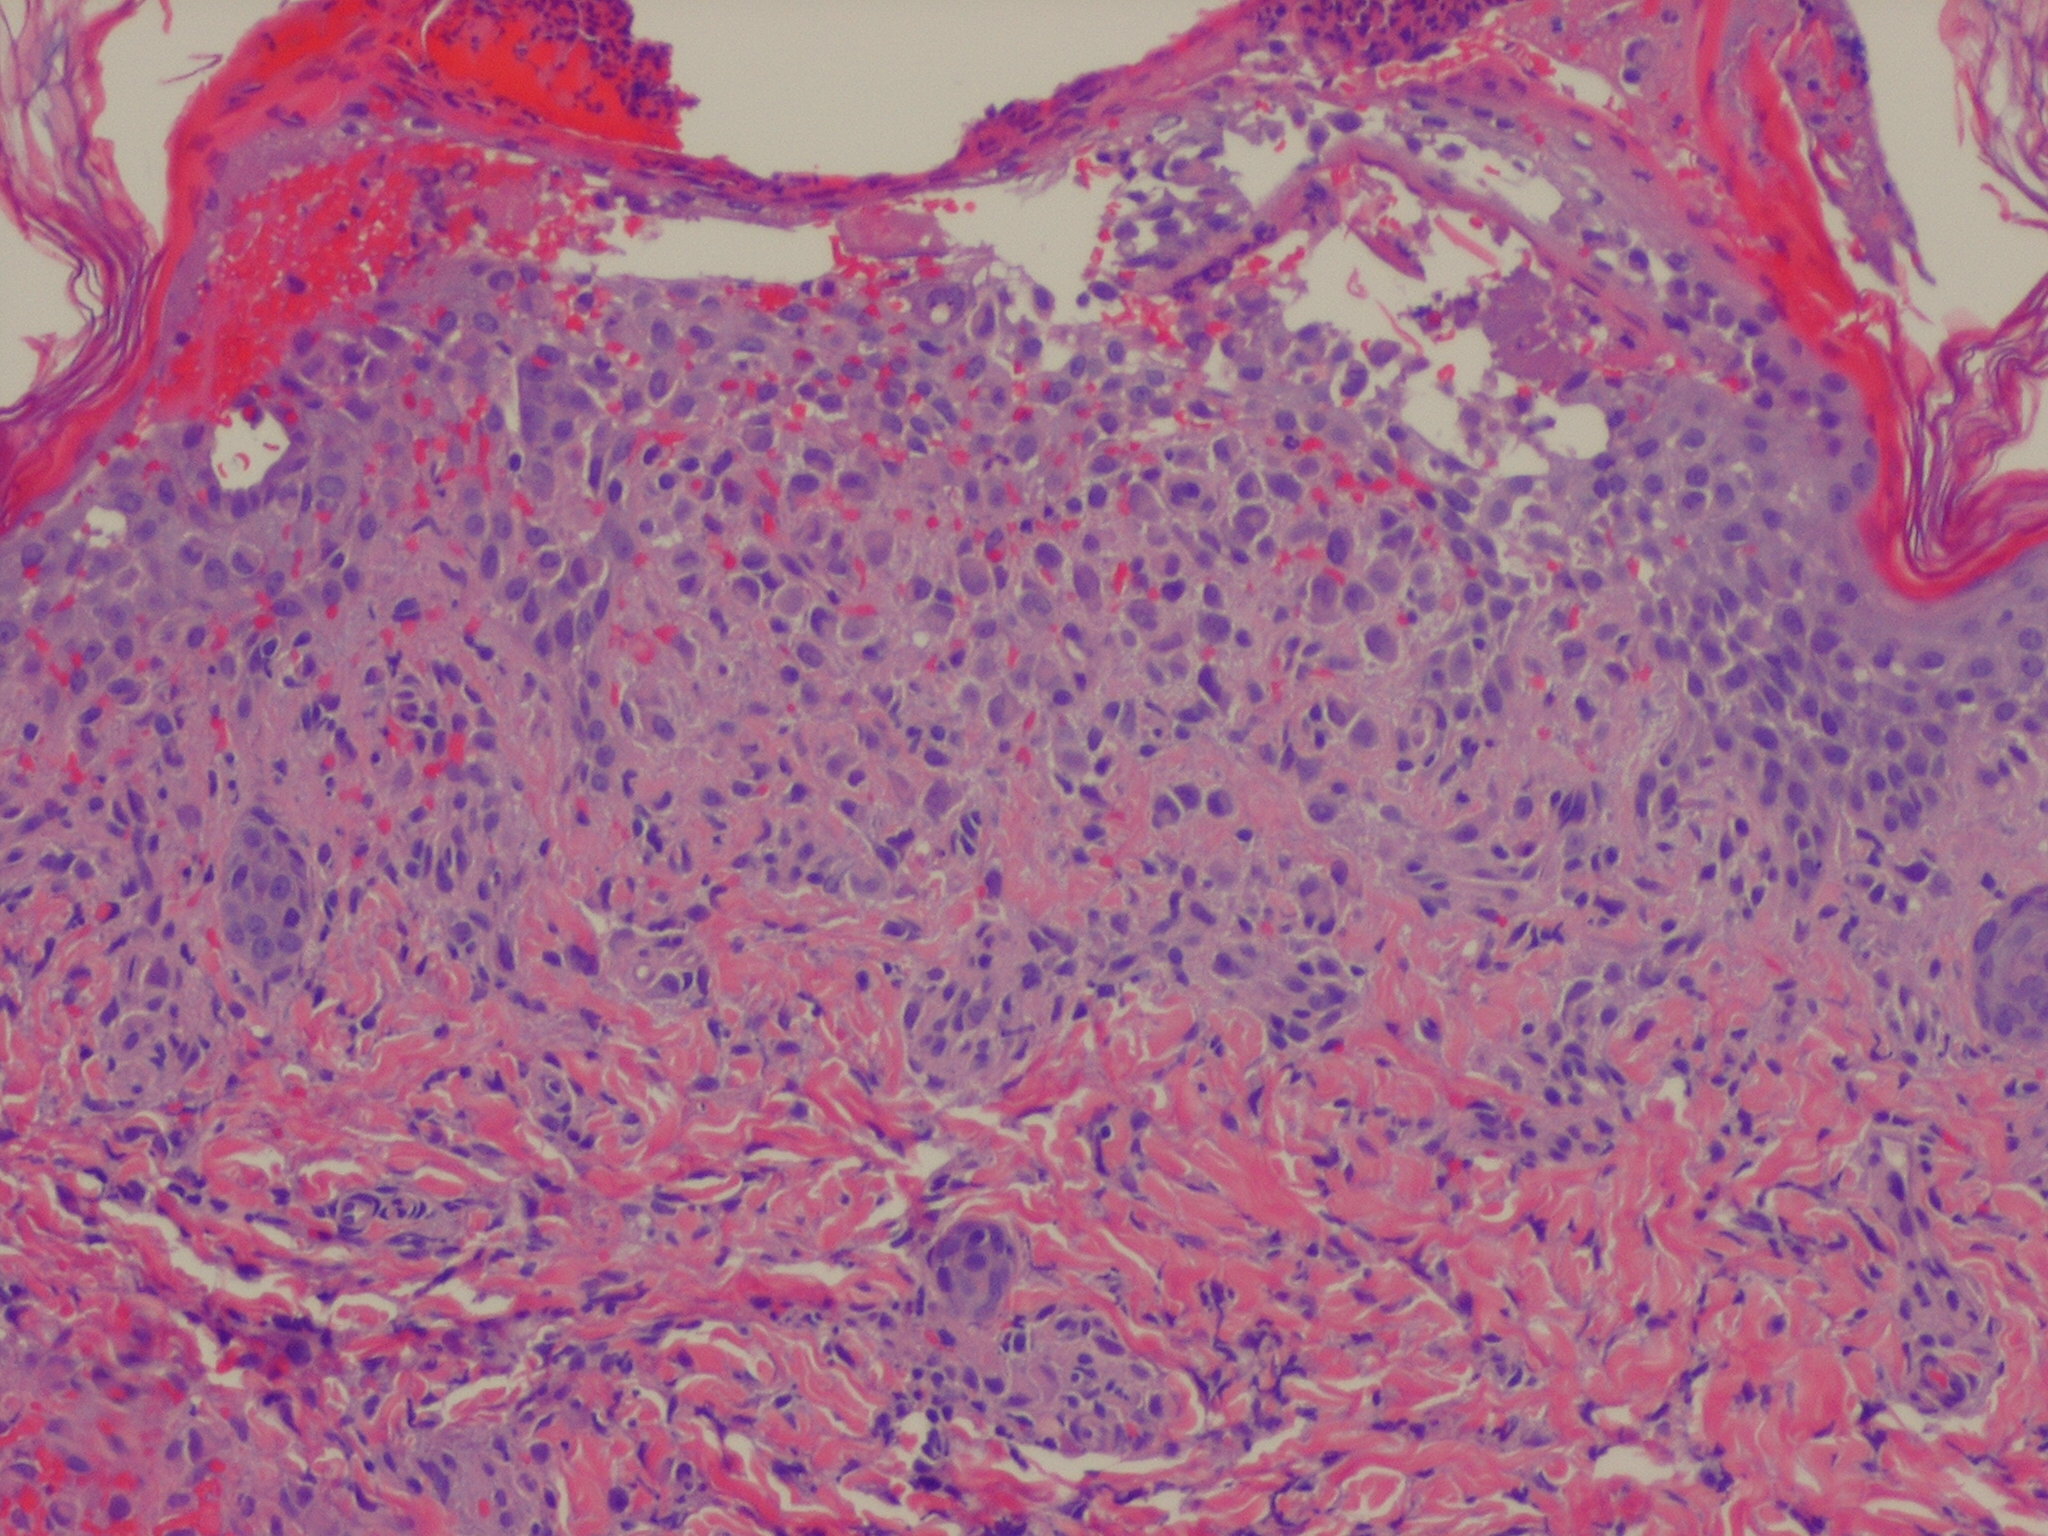

Langerhans cell histiocytosis = كثرة الخلايا الناسجة لانغرهانس

OLYMPUS DIGITAL CAMERA